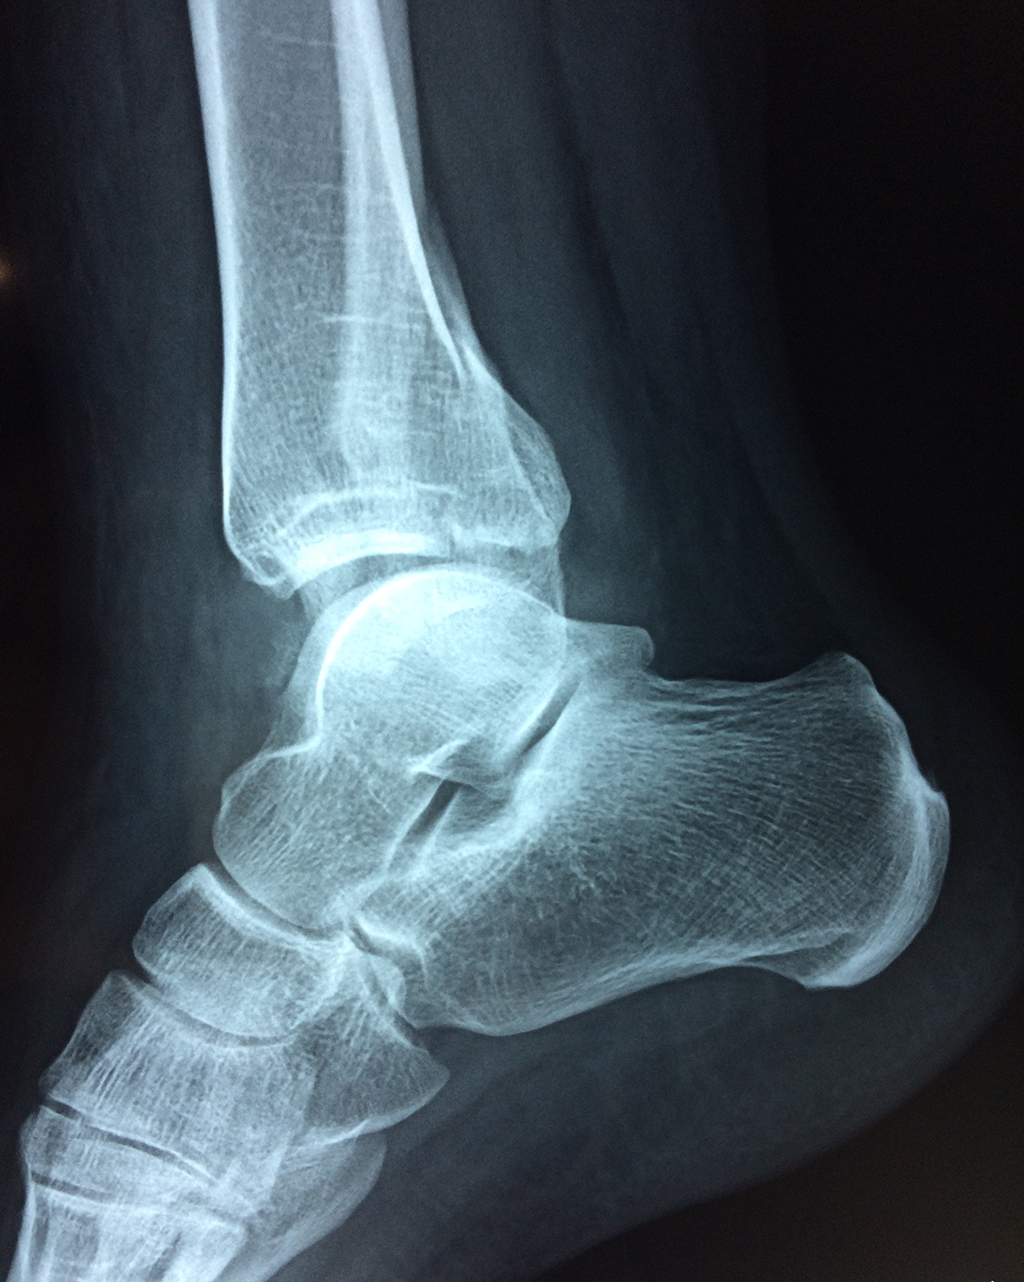

Una fractura de tobillo es la rotura de uno o más de los huesos del tobillo. Estas fracturas pueden ser:

- Los extremos de los huesos están desalineados entre sí (desplazados).

- La fractura se extiende hasta la articulación del tobillo (fractura intra-articular).